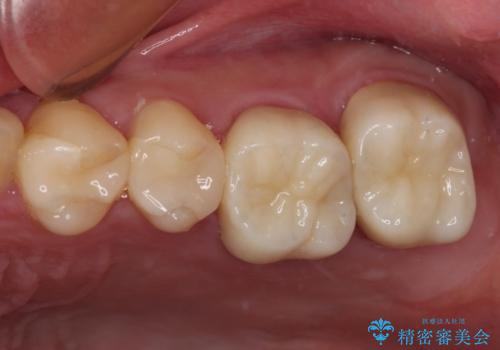

指摘された虫歯 オールセラミッククラウンによる補綴治療